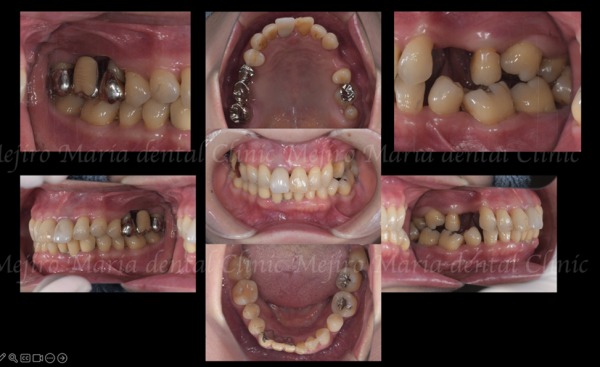

患者様は50代女性で、右上の歯肉の腫れと歯の動揺を主訴に来院されました。

正面からの見た目だけでは一見問題が無いように見えるものの、以前左側の複数の歯を抜歯したまま放置していたため、歯が前方に傾斜し、噛み合わせが大きく崩れていました。

長期間、噛み合わせの悪い左側を避けて右側だけで噛んでいたことにより、右上の歯周病が過度な力によって進行したものと考えられます。

この時点での問題点:

・右上の歯は保存できる状態ではない

・右上の咬合支持喪失により両側臼歯の機能が破綻している

・その結果、前歯へ過剰な負担が移行し、将来的に歯周病で多くの歯が喪失されることが予想される